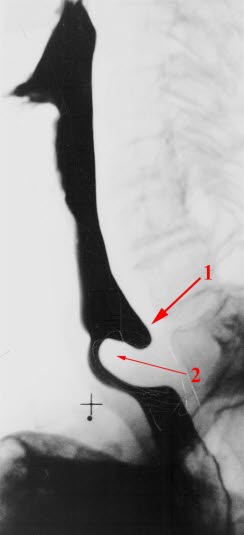

Zenkers divertikkel

Utposning baktil i nedre del av spiserøret (1)

Utposningen skyldes en svekkelse i musculus cricopharyngeus (2)